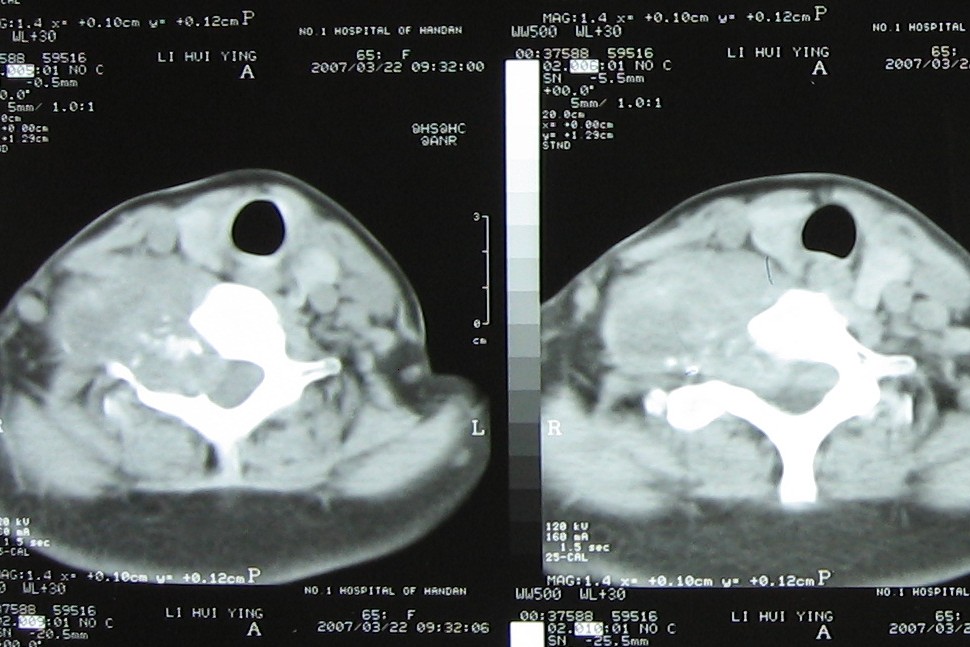

标题: CT7396:病人女65岁主因颈部肿疼伴上肢麻木4年近来加重入院 [打印本页]

标题: CT7396:病人女65岁主因颈部肿疼伴上肢麻木4年近来加重入院

支持考虑:神经原性肿瘤。(右侧椎间孔扩大,椎板破坏,局部明显的软组织肿块,并与椎管 神经根关系密切。)

支持考虑:神经源性肿瘤(右侧椎间孔扩大,椎板破坏,局部明显的软组织肿块,并与椎管神经根关系密切)。